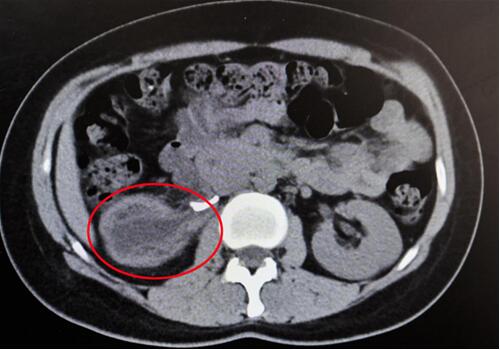

紅圈部分為手術后腎臟輪廓逐漸清晰。院方供圖

終于,功夫不負有心人,他們在粘連嚴重的腹膜外組織中找到了輸尿管!當時,靳文生主任心里緊繃的一根弦終于松了下來,接下來的手術過程也變得順暢了。

“雖然耗費了很多時間,但好在結局非常成功!苯纳魅握f,能為患者保住腎臟,花費再多時間也覺得值得。